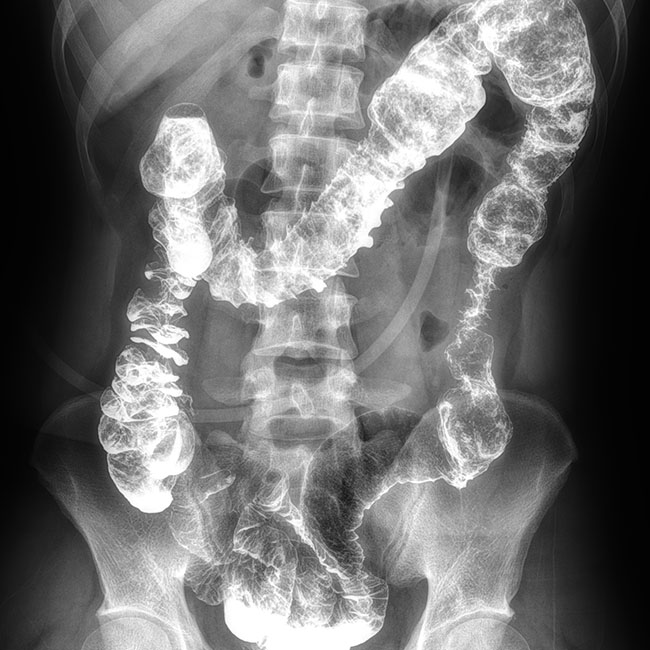

全自動狹縫拼接功能

垂直投影無畸變,反映真實骨骼結構

一鍵快速全脊柱/全下肢全景成像支持臥位和站立位檢查,成像劑量低

臨床樣本